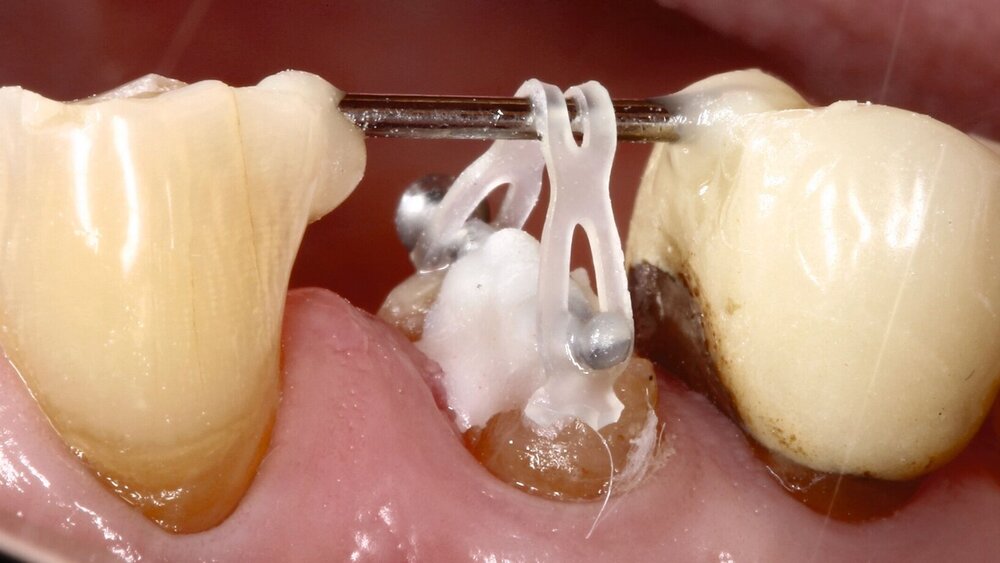

Die „hoffnungslosen Zähne“ wurden nach Kariesexkavation so vorbereitet, dass sie über eine Retention an den Nachbarzähnen mit Hilfe von kieferorthopädischen Gummizügen extrudiert werden konnten. Gleichzeitig wurden ein Scaling und eine Wurzelglättung durchgeführt sowie die suprakrestalen Fasern durchtrennt, um den Zahn möglichst ohne Weichgewebe zu bewegen. Nach der Retentionsphase wurden die Zähne, wenn nötig, mit einem Glasfaserstift und anschließend alle Zähne mit Kronen aus Lithiumdisilikat versorgt.